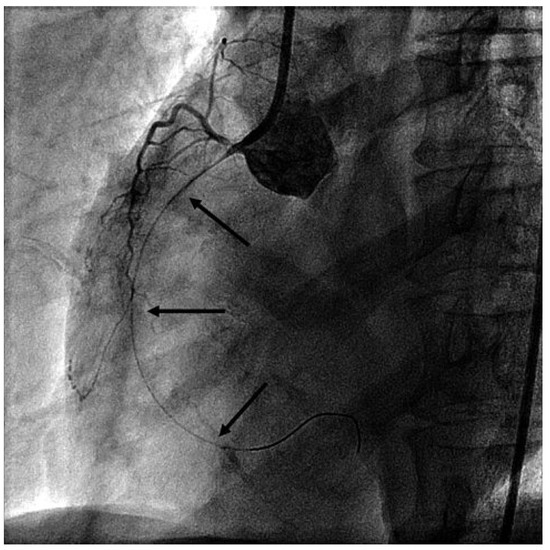

Giant Apical Aneurysm without Coronary Artery Disease

by Stéphane Chevallier and Jean-Christophe Stauffer

Abstract

A 66-year-old patient with some years’ history of apical hypertrophic cardiomyopathy treated by beta-blockers attended for follow-up echocardiography [...] Full article

Malignant Arrhythmia Associated with Chest Pain and a Diagnosis of Myocarditis

by Stéphane Noble, David Carballo and Haran Burri

A 51-year-old lady had been admitted 9 months previously with typical chest pain occurring at rest associated with transient palpitations and dizziness [...] Full article

The differential diagnosis of recurrent chest pain is manifold. Although it is unlikely in younger people, a cardiac origin should always be considered. We report a case of recurrent chest pain which was initially considered to have a gastrointestinal or psychic origin. A [...] Read more.

The differential diagnosis of recurrent chest pain is manifold. Although it is unlikely in younger people, a cardiac origin should always be considered. We report a case of recurrent chest pain which was initially considered to have a gastrointestinal or psychic origin. A circadian pattern of the pain was conspicuous. Finally, coronary angiography performed in the setting of an acute coronary syndrome followed by life-threatening rhythm disturbances established the diagnosis. Full article

Show Figures

Figure 1